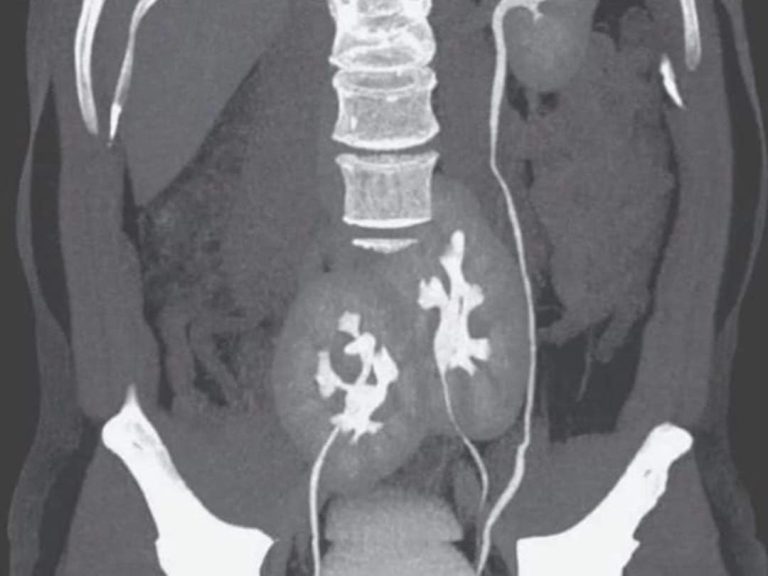

Cursos para comprender la correcta interpretación de placas ultrasonidos y radiografías, por medio de placas reales de mastografia, ultrasonidos, radiografias, etc.

Tomografía Axial Computada

Oportunidades de formación adaptadas a las necesidades de cada alumno.